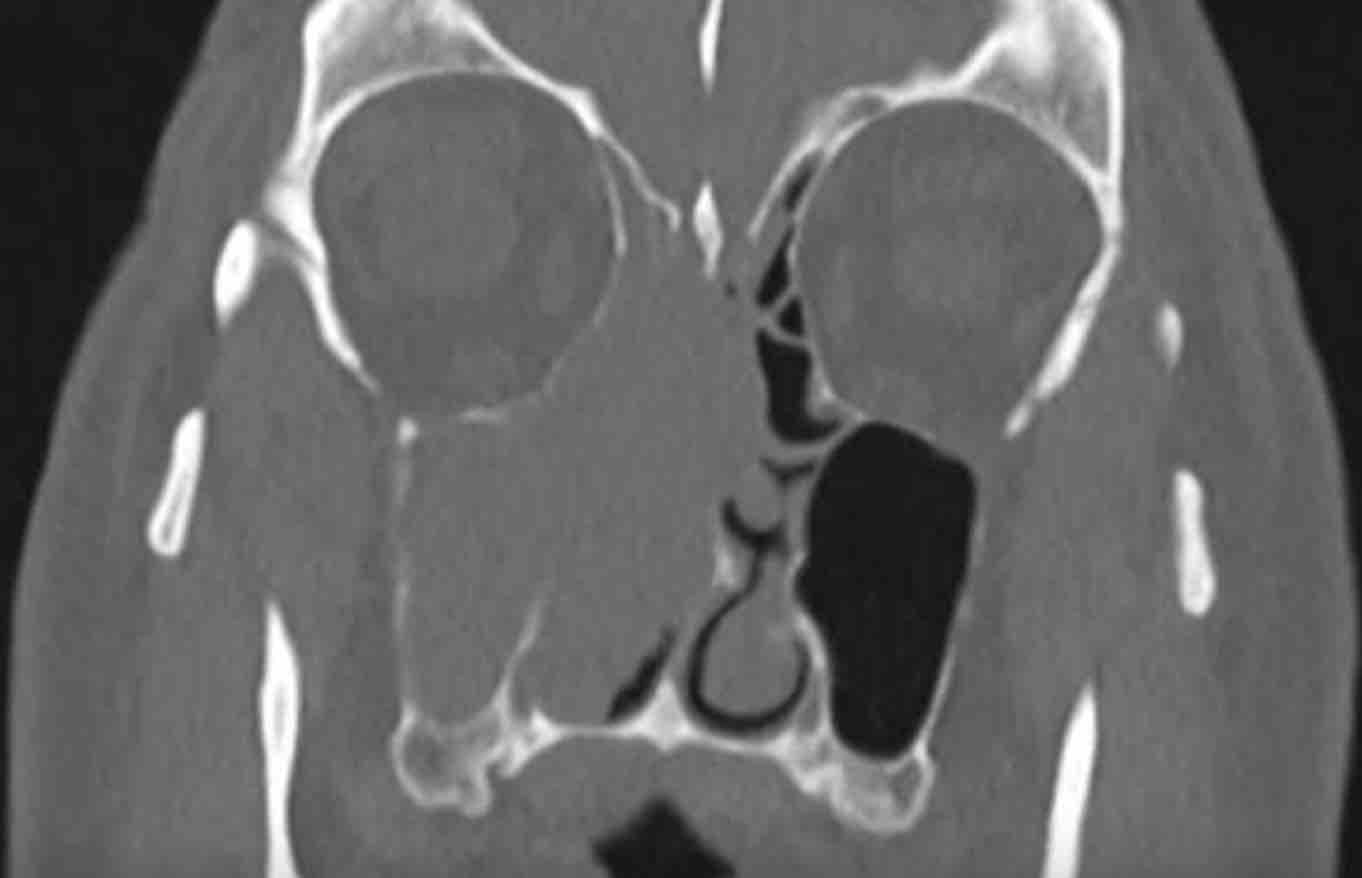

Các hình ảnh này của bệnh nhân nam 47 tuổi, có triệu chứng căng tức vùng trán.

- Tổn thương giãn rộng đẩy nhãn cầu trái sang bên.

- Tổn thương có bờ rõ nét.

- Tổn thương xuất phát từ xoang trán trái.

- Thành trong hốc mắt trái (đầu mũi tên đen) và nền sọ (đầu mũi tên trắng) bị mỏng đi, nhưng không có phá hủy xương.